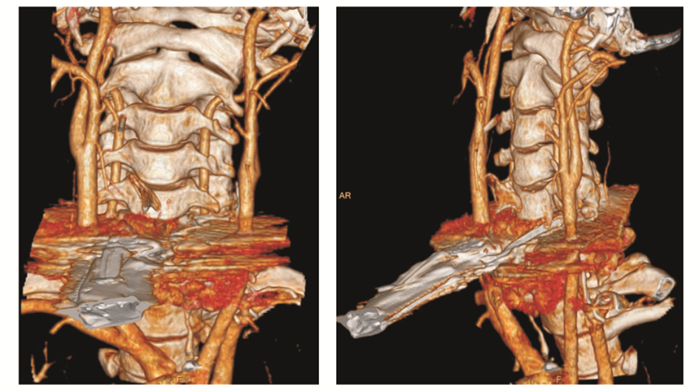

(1) 血管损伤:伤口无大出血,未触及有进行性的扩张性血肿或波动性血肿,无血管杂音和震颤,伤侧远端无动脉搏动减弱或消失。颈部三维血管重建结果(图 2):存在较多尾影,效果差,大体可见双侧颈动脉完整,但无法判断是否存在浅表细小动静脉损伤。见图 2、图 3、图 4。患者偏瘫、偏侧感觉减弱,为血管损伤?为脊髓损伤?

|

| 图 2 患者颈部血管三维立体重建结果 |

|

|